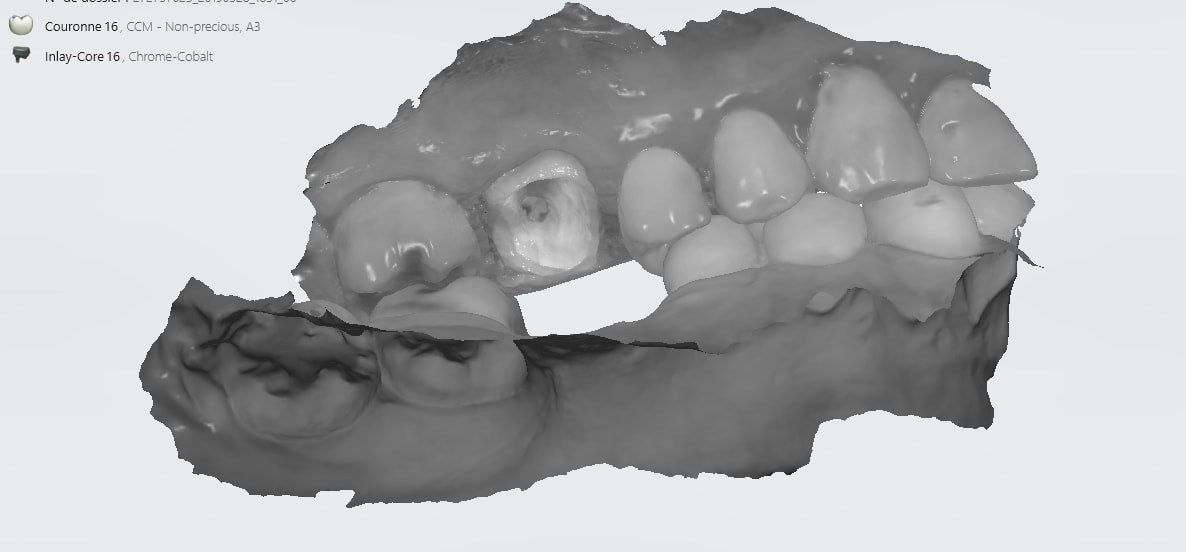

IC ceram 23 + stellite.

Idem que Chicot: Oneshot mais avec un peu plus d’éléments : 3IC, 8 CCM, 1 Stelitte. Aucune retouche autre qu’occlusale. Même Labo, c’est basique mais efficace

Pas mal. Attachements + augmentation de DV en plus.